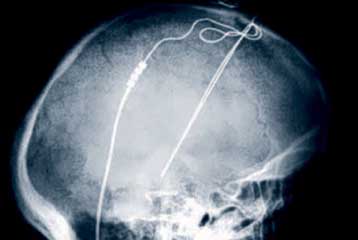

Έπειτα από τα εγκεφαλικά εμφυτεύματα για την αντιμετώπιση της κατάθλιψης και της νόσου του Πάρκινσον, η αμερικανική Υπηρεσία Τροφίμων και Φαρμάκων (FDA) ενέκρινε μια παρόμοια συσκευή που ίσως βοηθά στην καταπολέμηση της ιδεοψυχαναγκαστικής διαταραχής.